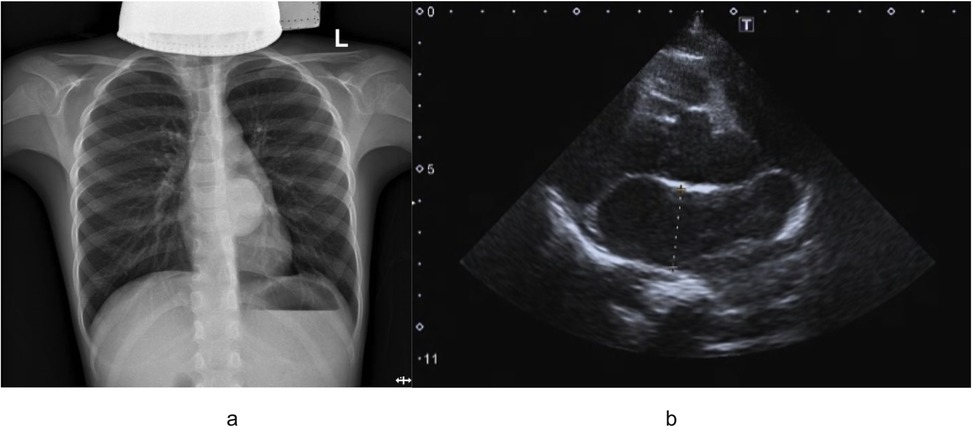

An 8-year-old boy presented with a one-week history of intermittent left-sided chest pain, bloating, and nausea. On physical examination, all findings were within normal ranges except for left chest tenderness and slightly restricted respiratory movements. Preoperative imaging included chest radiography, US, and PET/CT. The chest radiograph demonstrated a high-density mediastinal shadow, while US identified a 55*48*37 mm posterior mediastinal mass in the suprasternal region (Figure 1). Subsequent PET/CT further characterized a 37*31*37 mm paraspinal cystic lesion in the left lower lobe with loss of metabolism, confirming the need for surgical resection (Figure 2). Laboratory studies indicated no contraindications to surgery.

Figure 1. (a) Outcomes of preoperative chest radiograph demonstrated a high-density mediastinal shadow; (b) preoperative ultrasound examination indicated left posterior mediastinal mass lesion.